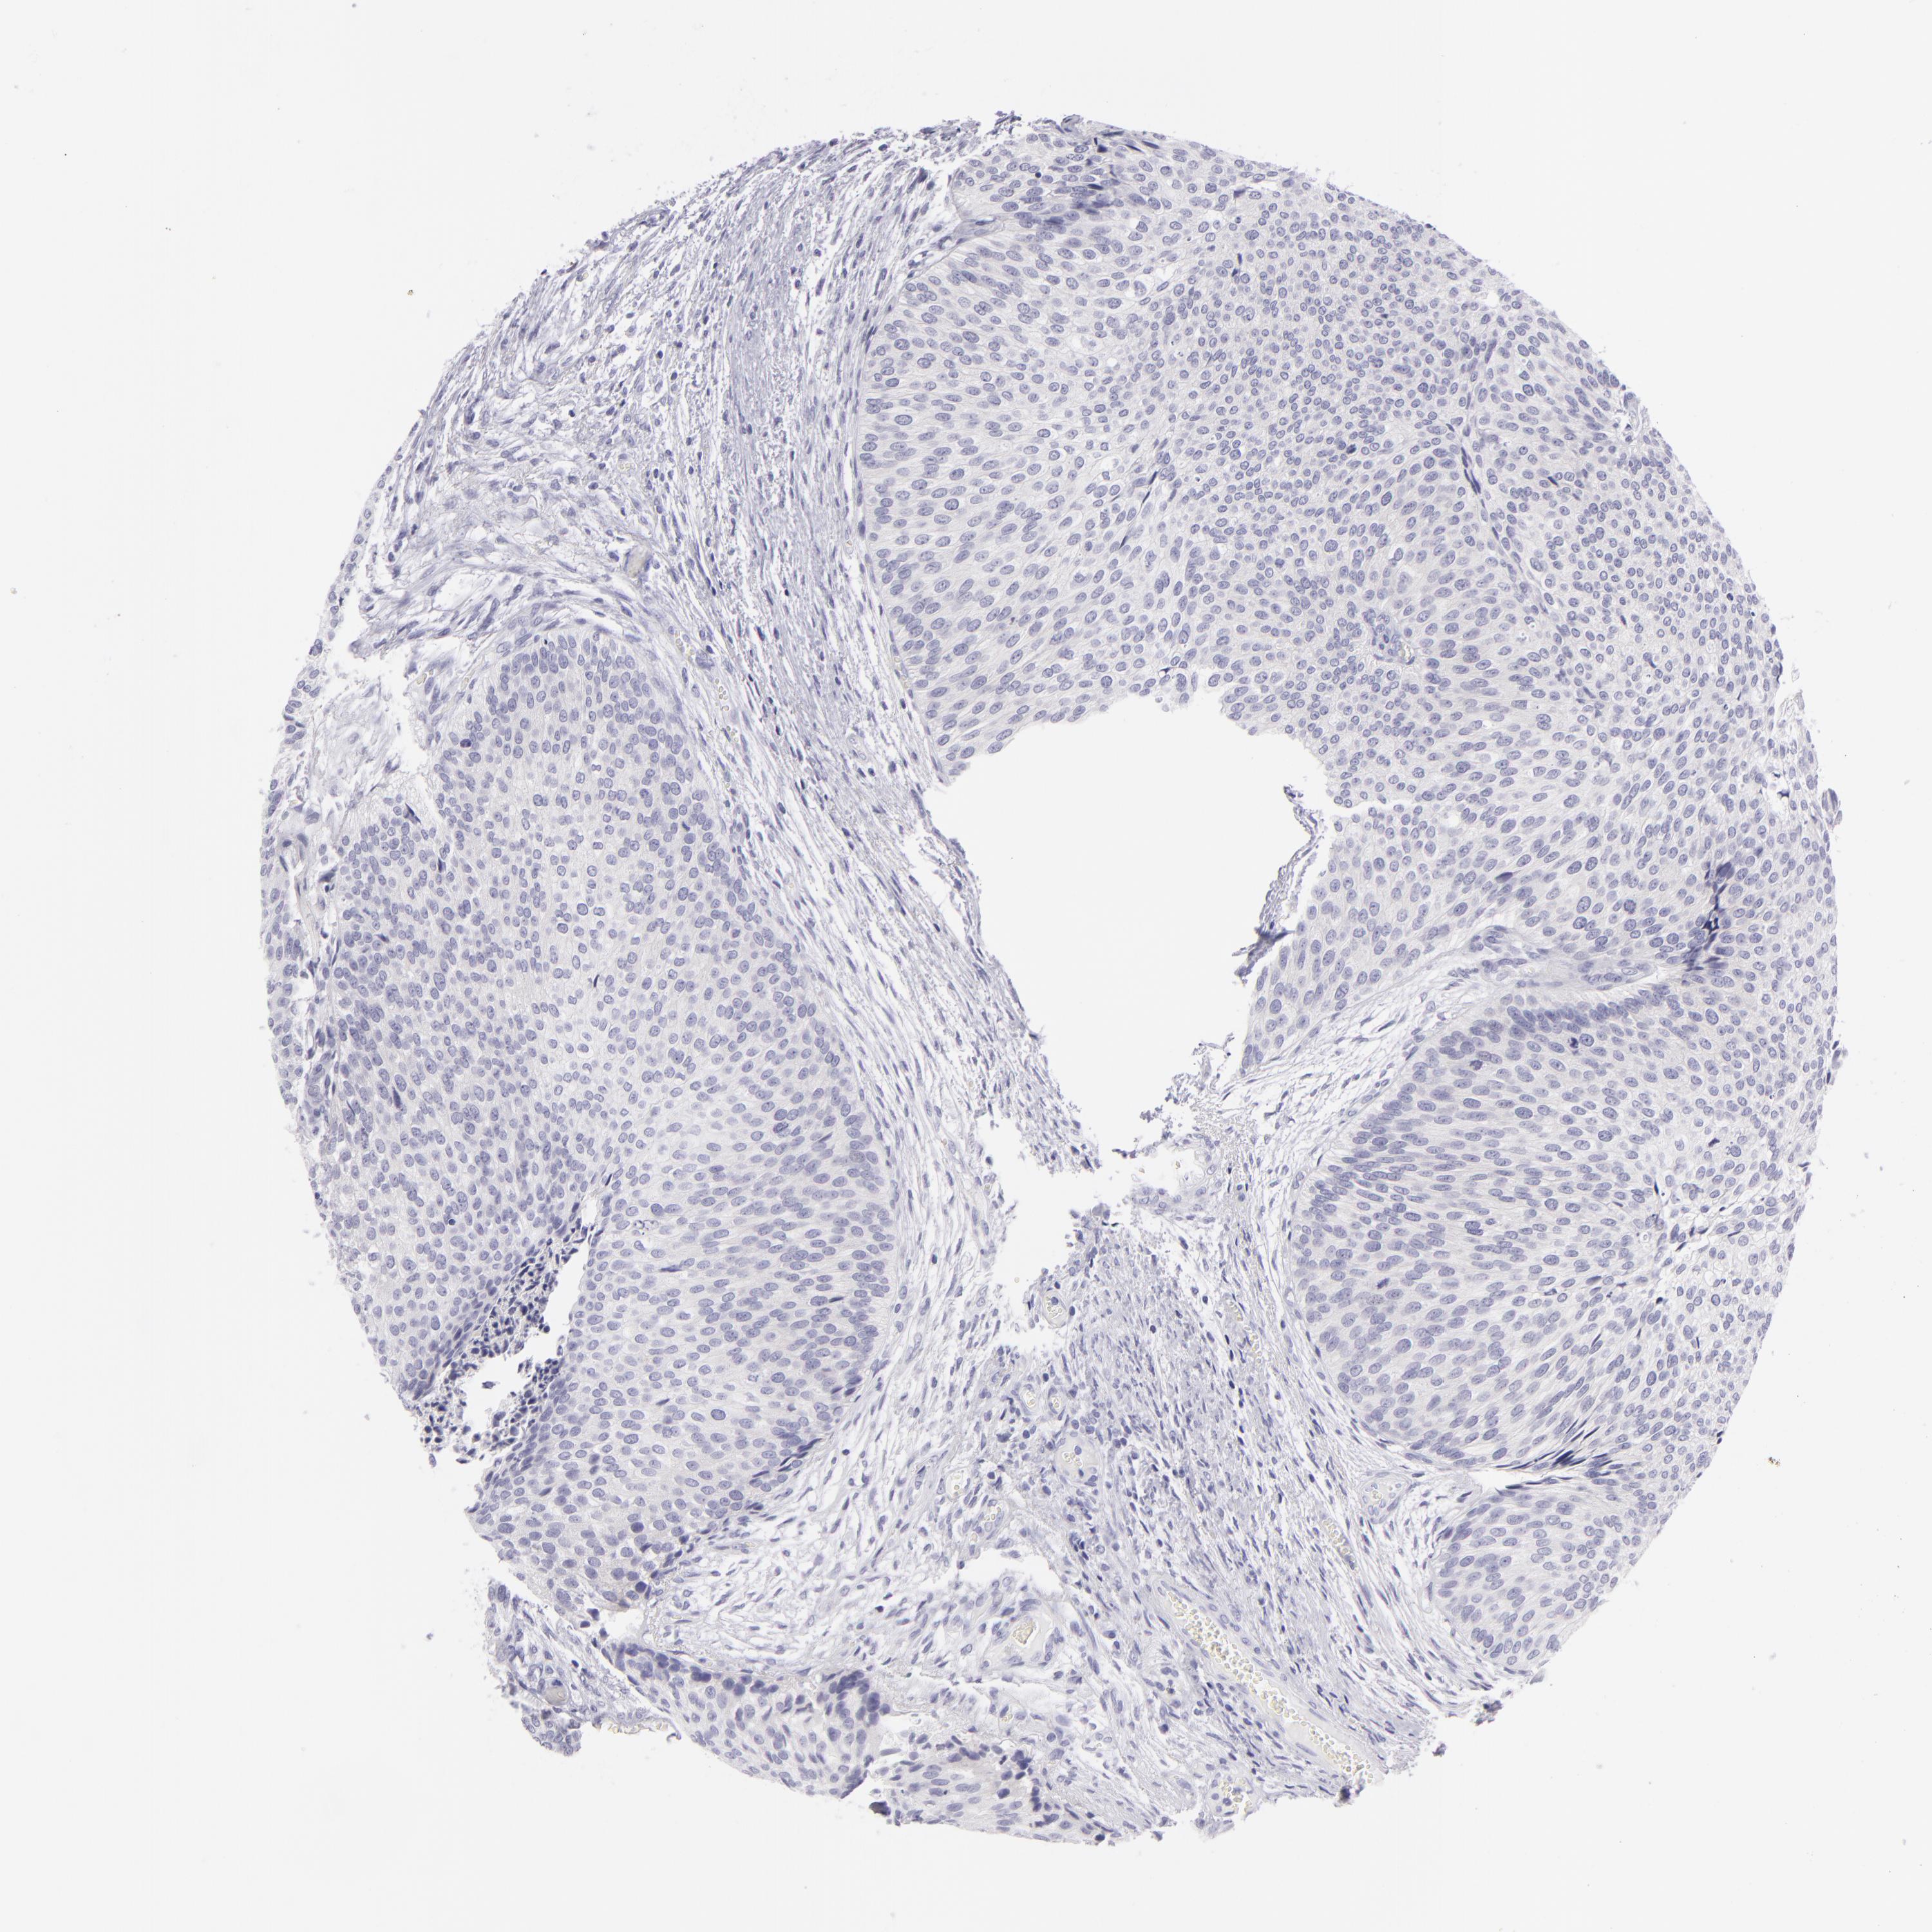

UROTHELIAL CANCER - Protein expressioni

A mouse-over function shows sample information and annotation data. Click on an image to view it in a full screen mode. Samples can be filtered based on level of antibody staining by selecting one or several of the following categories: high, medium, low and not detected. The assay and annotation is described here.

Note that samples used for immunohistochemistry by the Human Protein Atlas do not correspond to samples in the TCGA dataset.

Antibody stainingi

Antibody staining in the annotated cell types in the current human tissue is reported as not detected, low, medium, or high, based on conventional immunohistochemistry profiling in selected tissues. This score is based on the combination of the staining intensity and fraction of stained cells.

Each image is clickable and will lead to virtual microscopy that enables deeper exploration of all samples and also displays staining intensity scores, fraction scores and subcellular localization as well as patient and tissue information for each sample.

Antibody HPA010122

Antibody HPA071006

Antibody CAB001999

Antibody CAB002000

Urothelial carcinoma, Low grade

Urothelial carcinoma, High grade

Urothelial carcinoma, NOS

Adenocarcinoma, NOS